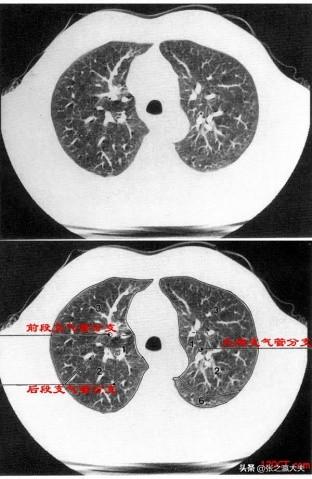

従来、肺がん患者の症状は、咳が出る、血を吐く、筋肉が黄色くやせる、食欲不振、さらには顔や足がむくむ、呼吸が苦しくなるなど、もっと深刻なものと思われていた。しかし、これらは進行した、あるいは末期の肺がん患者の症状である。実のところ、人々の健康観念の向上に伴い、肺がんはますます早期発見されるようになってきている。早期の肺がんと診断される患者さんも増えています。このような人たちは基本的に自覚症状がないので、どうやって肺がんだとわかるのでしょうか?胸部低線量スパイラルCT検査です!このCT検査は、胸部X線写真よりも早く、いくつかの小さな悪性結節を発見することができます。